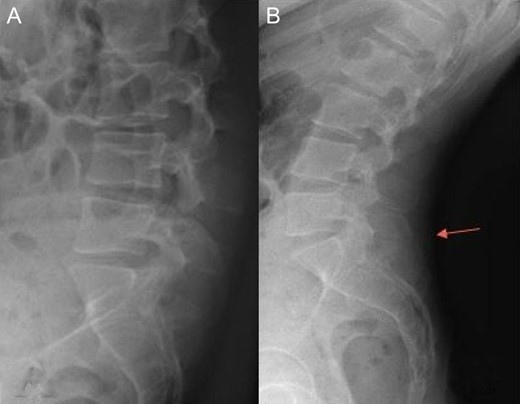

Radiography of the spine revealed an asymmetry of pelvis (Fig. 1), and despite a report refuting Baastrup’s disease, we can see a contact between spinous processes of L5 and S1 in extension (Fig. 2).

Radiography of lumbar spine in anterior-posterior and lateral views showing asymmetry of pelvis.